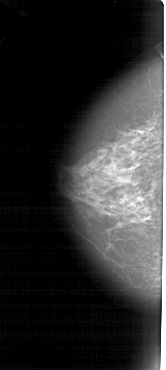

A_1277_1.RIGHT_MLO

RIGHT_MLO LINES 5026 PIXELS_PER_LINE 2206 BITS_PER_PIXEL 12 RESOLUTION 43.5 OVERLAY

FILE: A_1277_1.RIGHT_MLO.OVERLAY

TOTAL_ABNORMALITIES 1

ABNORMALITY 1

LESION_TYPE MASS SHAPE IRREGULAR MARGINS ILL_DEFINED

ASSESSMENT 4

SUBTLETY 5

PATHOLOGY BENIGN